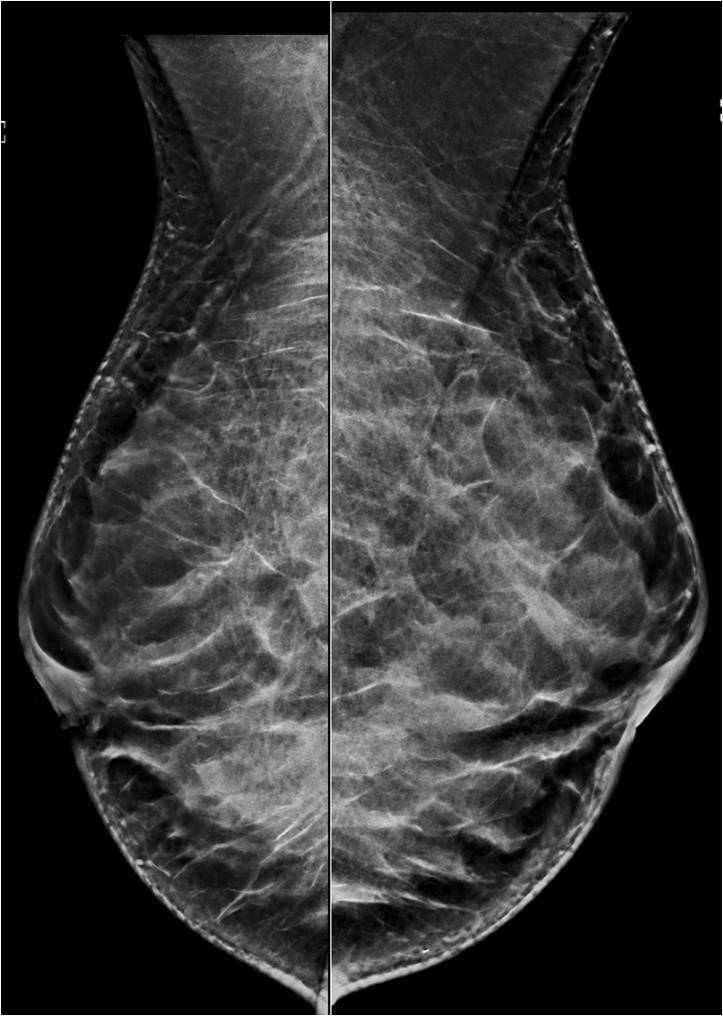

Improved detection of breast cancer with automated breast ultrasound, according to study.

Ultrasound detects more invasive cancers, but number of total cancers detected is comparable between US and mammography.

Radiologists viewing supplemental breast ultrasounds should assess lesions separately to reduce the risk of missing a cancer.